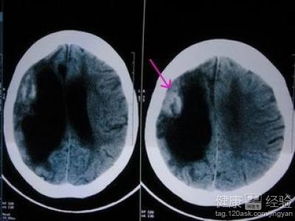

我國腦梗死后70%~80%的患者因為殘疾而不能獨立生活?目前醫(yī)學(xué)界比較公認的導(dǎo)致腦梗死高致殘率的一個重要因素是忽視腦梗死急性期的康復(fù)治療?根據(jù)發(fā)病時間腦梗死可分為5期:超急性期(<6小時)、急性期(6小時-3天)、亞急性期(3天-10天)、早期慢性期(10天-1個月)、晚期慢性期(>1個月)。起病6小時以內(nèi)的超急性期腦梗死的診斷或提示診斷尤為重要。腦梗死患者發(fā)病后就應(yīng)該開始康復(fù)干預(yù),這能夠減輕患者功能殘疾,加速恢復(fù)進程,此時要尤其注意康復(fù)護理,關(guān)注患者意識是否清醒、吞咽功能是否恢復(fù),注意患者的體位要合理,并經(jīng)常變換不同的體位,即使患者肢體不能活動,也要幫助其在床上進行被動運動。